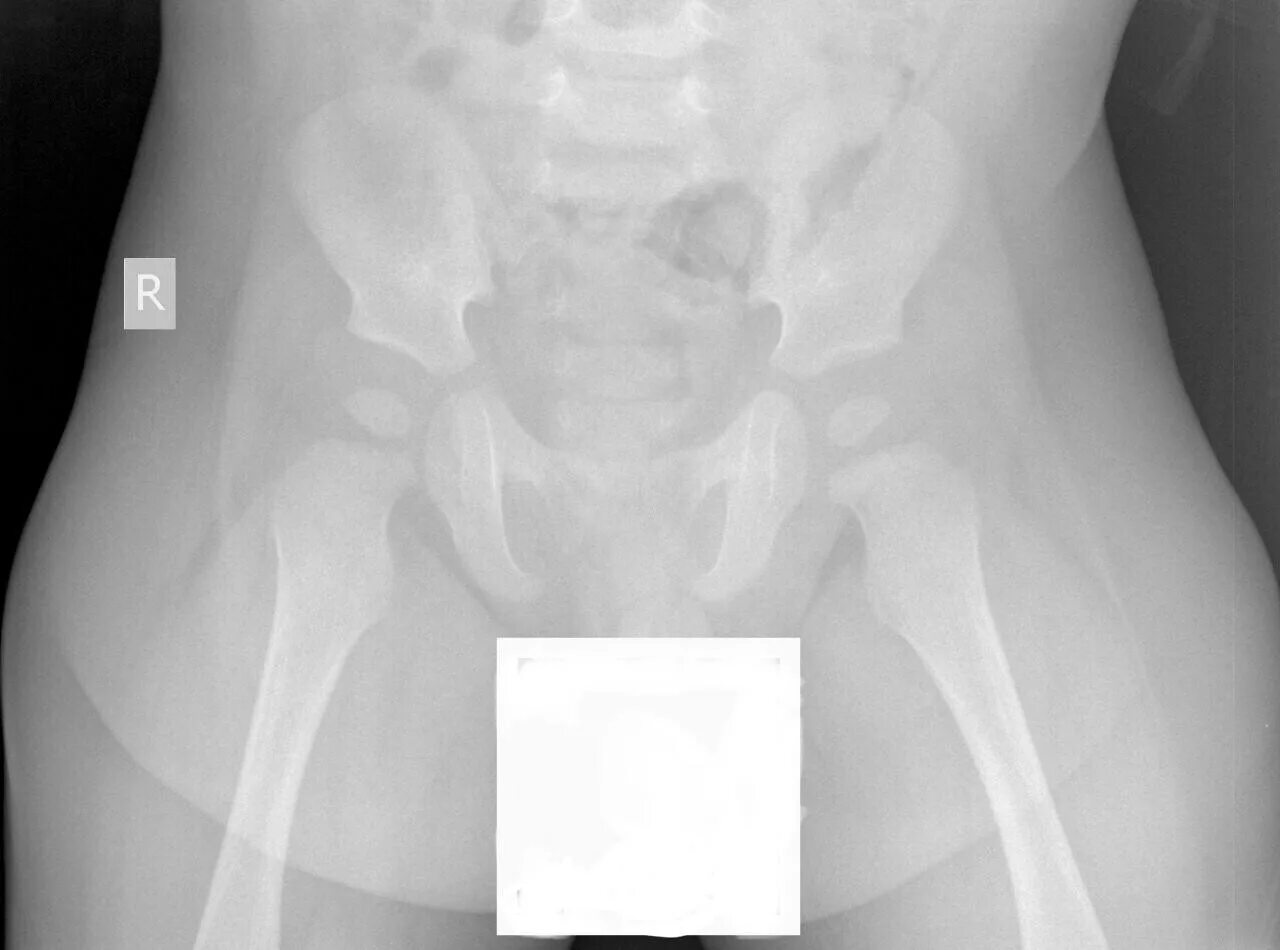

Дисплазия 7 лет